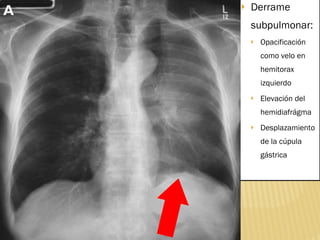

Derrame subpulmonar: Opacificación como velo en hemitorax izquierdo Elevación del hemidiafrágma Desplazamiento de la cúpula gástrica

Derrame subpulmonar: Opacificacióncomo velo en hemitorax izquierdo Elevación del hemidiafrágma Desplazamiento de la cúpula gástrica